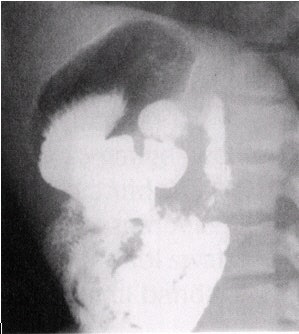

![]() |

| Stomach images in which the upper two images are obtained with compression. The bottom two images are superior body and fundus, which, being under the ribs, cannot be compressed. Image courtesy of Dr. Naveed Ahmad. |